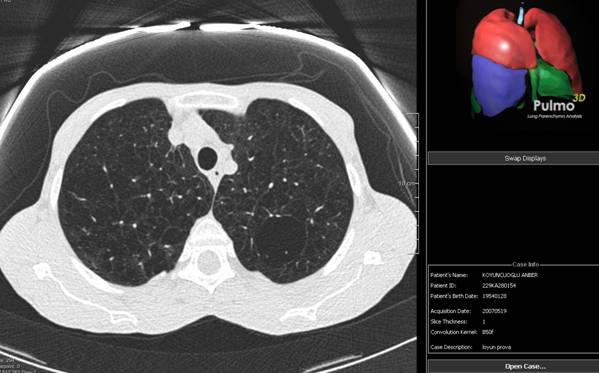

I parametri TC sono stati i seguenti: 120 Kvp, 20 mAs, tempo di rotazione 0.42 s, collimazione 0.75 mm con ricostruzione a 1 mm. E' stato utilizzato un software che fornisce la densità polmonare e la volumetria. Utilizzando procedure automatiche abbiamo isolate il parenchima polmonare dal mediastino e dalla parete toracica applicando il range di -200 / -1024 HU. Successivamente il polmone è stato diviso in sub-range di densità con una soglia di -910/-1024 HU per l'enfisema e -200/-500 HU per lesioni tumorali, atelettasie o zone di perdita aerea non riferibili a tumori come accade per la fibrosi polmonare. Il computer ha calcolato il volume totale del parenchima polmonare espresso in cm3 e successivamente la porzione di parenchima patologica. Due radiologi hanno valutato le immagini separatamente e i dati sono stati registrati al fine di valutare anche l'agreement tra gli osservatori. Le immagini sono state analizzate in una workstation dedicata (Leonardo Siemens) ed è stato utilizzato un software per la valutazione della crescita volumetrica (LungCare software Siemens).

Quantificazione dell'enfisema mediante TC e software MeVisPulmo

Le TC sono state esaminate mediante l'impiego di un software (MeVisPulmo, Bremen) che consente la misurazione totale del volume polmonare, la densità media, i pixel, il "bulla index" e l'analisi sia qualitativa che quantitativa dell'enfisema polmonare. La valutazione prevede la segmentazione delle vie aeree e del polmone. I dati processati vengono storati come immagini DICOM (Digital Imaging and Communications in Medicine). Alla fine della processazione dei dati i valori vengono visualizzati e trascritti in un report. Le regioni lobari vengono indicate con differenti colori nelle sezioni sagittali, coronali e assiali come indicato nella fig. 3-5.

Figura 3. Scansione TC 3D (postero-anteriore). Albero

tracheobronchiale (azzurro), lobi inferiori (verde), lobi superiori

(rosso). I valori di pixels ≤ a -950 HU (giallo), identificano le

zone di enfisema.

Figura 5. Immagine assiale con ripartizione dei segmenti

polmonari indicati con colori diversi.